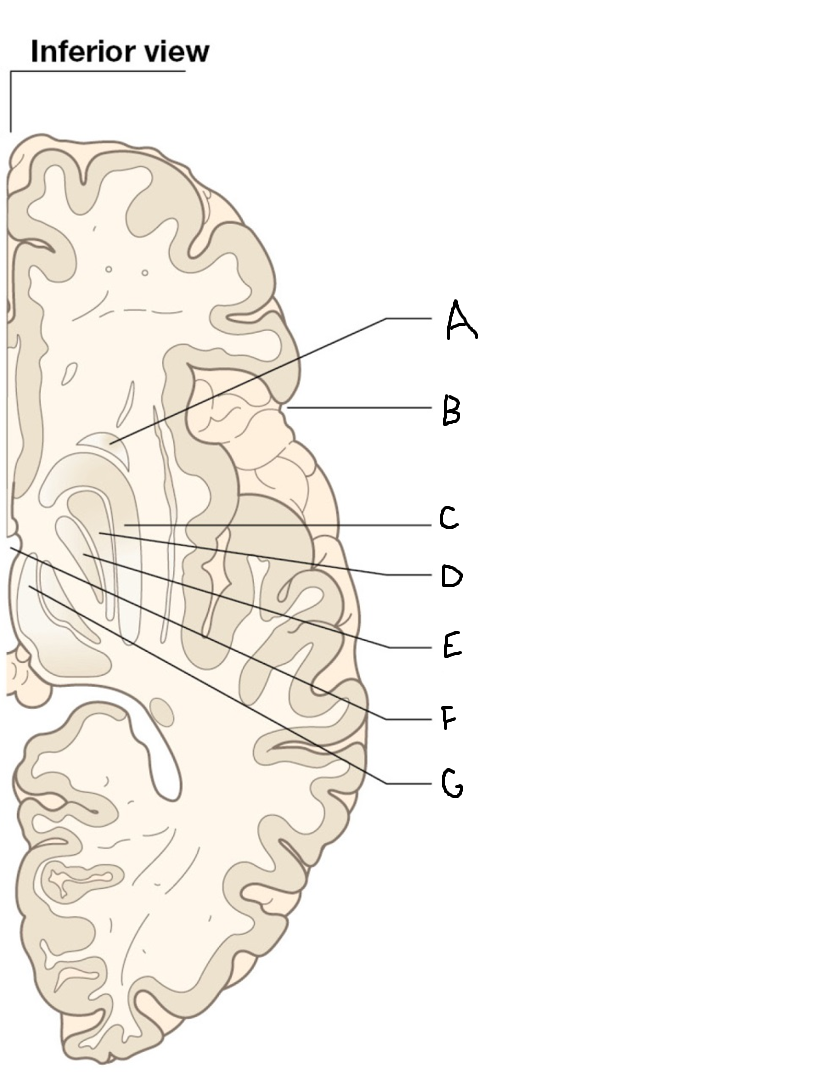

caudate nucleus head

A

Putamen

B

caudate nucleus tail

C

Lateral ventricle

D

caudate nucleus body

E

internal capsule

F